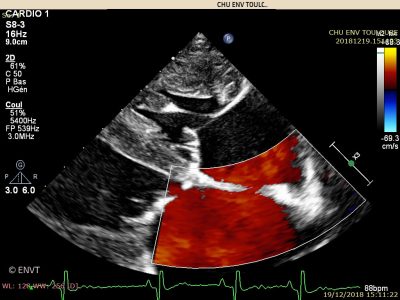

La cardiologie est la spécialité qui concerne l’état du coeur et du système vasculaire de l’animal. Les examens effectués au sein du service ont pour but de prévenir, diagnostiquer ou traiter des maladies cardiaques, vasculaires ou respiratoires.

Les consultations sont réalisées pour les chiens, chats, et NAC, que ce soit pour le diagnostic, le suivi ou le dépistage de cardiopathies (affections cardiaques) congénitales (présentes à la naissance) ou acquises (exprimées à l’âge adulte).